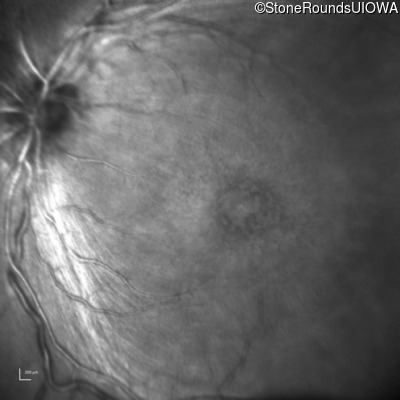

Infrared Fundus Photograph - Left - 10/40

Exemplar